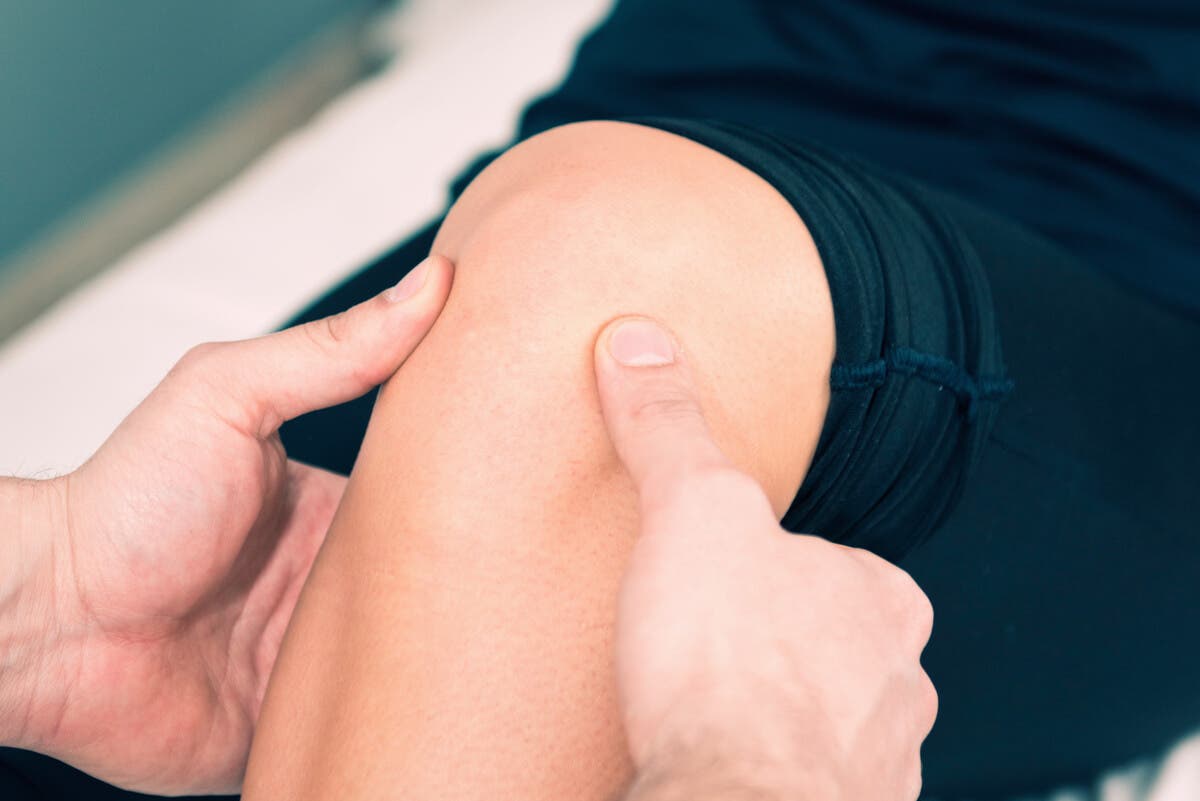

På den annen side oppstår klonus når kneskålen skyves nedover. For å gjøre dette må legen presse den ned med tærne. Siden det er en mer begrenset bevegelse, er den vanskeligere å observere enn i foten.